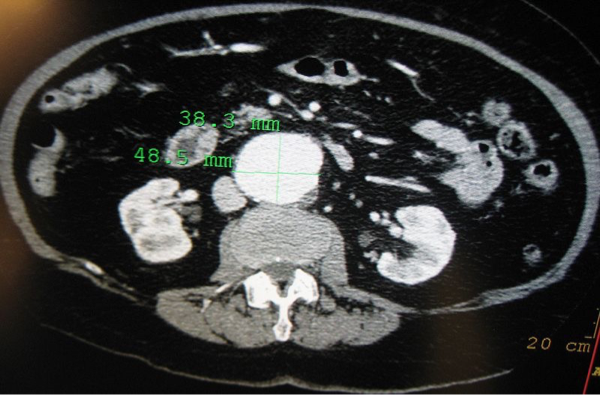

What does this CT refer to

Abdominal Aortic Aneurysm